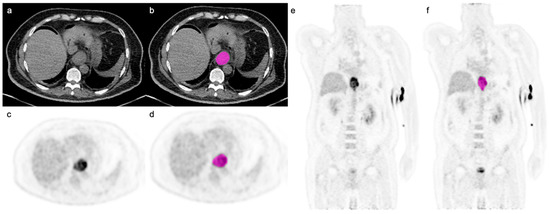

2.3. Image Segmentation and Radiomic Feature Extraction

- Anconina, R.; Ortega, C.; Metser, U.; Liu, Z.A.; Elimova, E.; Allen, M.; Darling, G.E.; Wong, R.; Taylor, K.; Yeung, J.; et al. Combined 18F-FDG PET/CT Radiomics and Sarcopenia Score in Predicting Relapse-Free Survival and Overall Survival in Patients with Esophagogastric Cancer. Clin. Nucl. Med. 2022, 47, 684–691. [Google Scholar] [CrossRef]